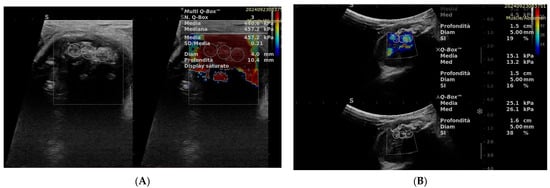

SWE has been extensively studied in various organs such as the liver and breast, demonstrating clinical utility in assessing liver fibrosis and characterizing breast lesions, respectively [24]. SWE provides the advantage of real-time assessment of tissue elasticity, enabling a more comprehensive characterization of lesions. Malignant tumors often demonstrate heightened tissue stiffness attributed to factors such as increased cellularity, enhanced extracellular matrix deposition, and alterations in tissue architecture (Figure 2).

Figure 2. SWE of STTs (A): malignant tumor with high stiffness; (B): benign lesion with low stiffness.